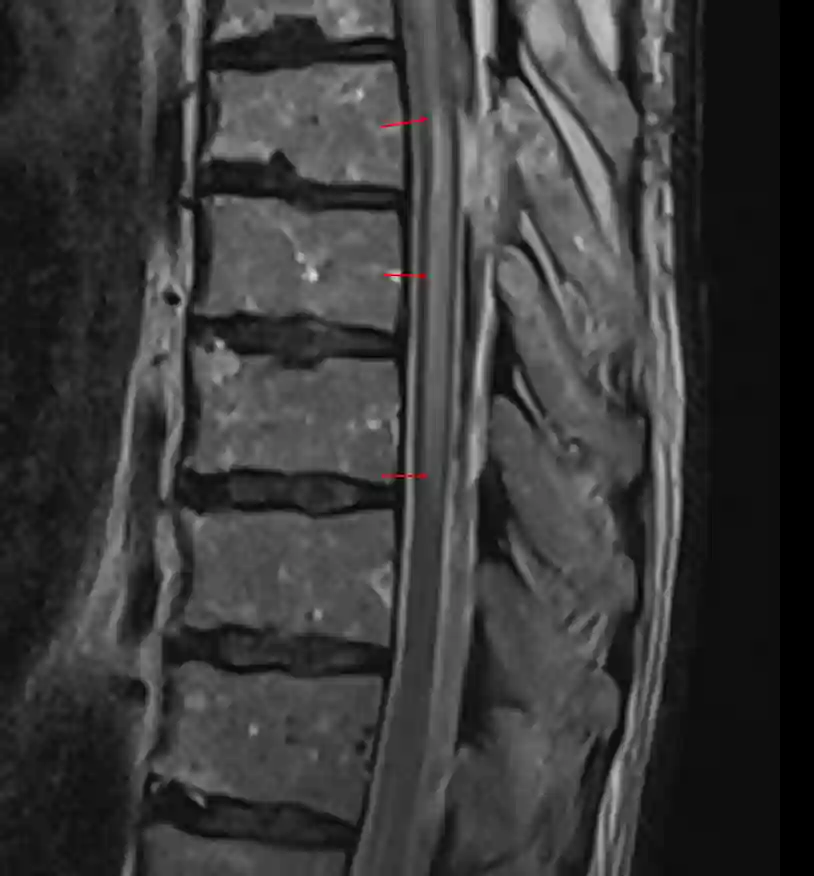

Myelopathie im MRI

Darstellung einer mehrsegmentalen Myelopathie in einer T2 MRI Sequenz.